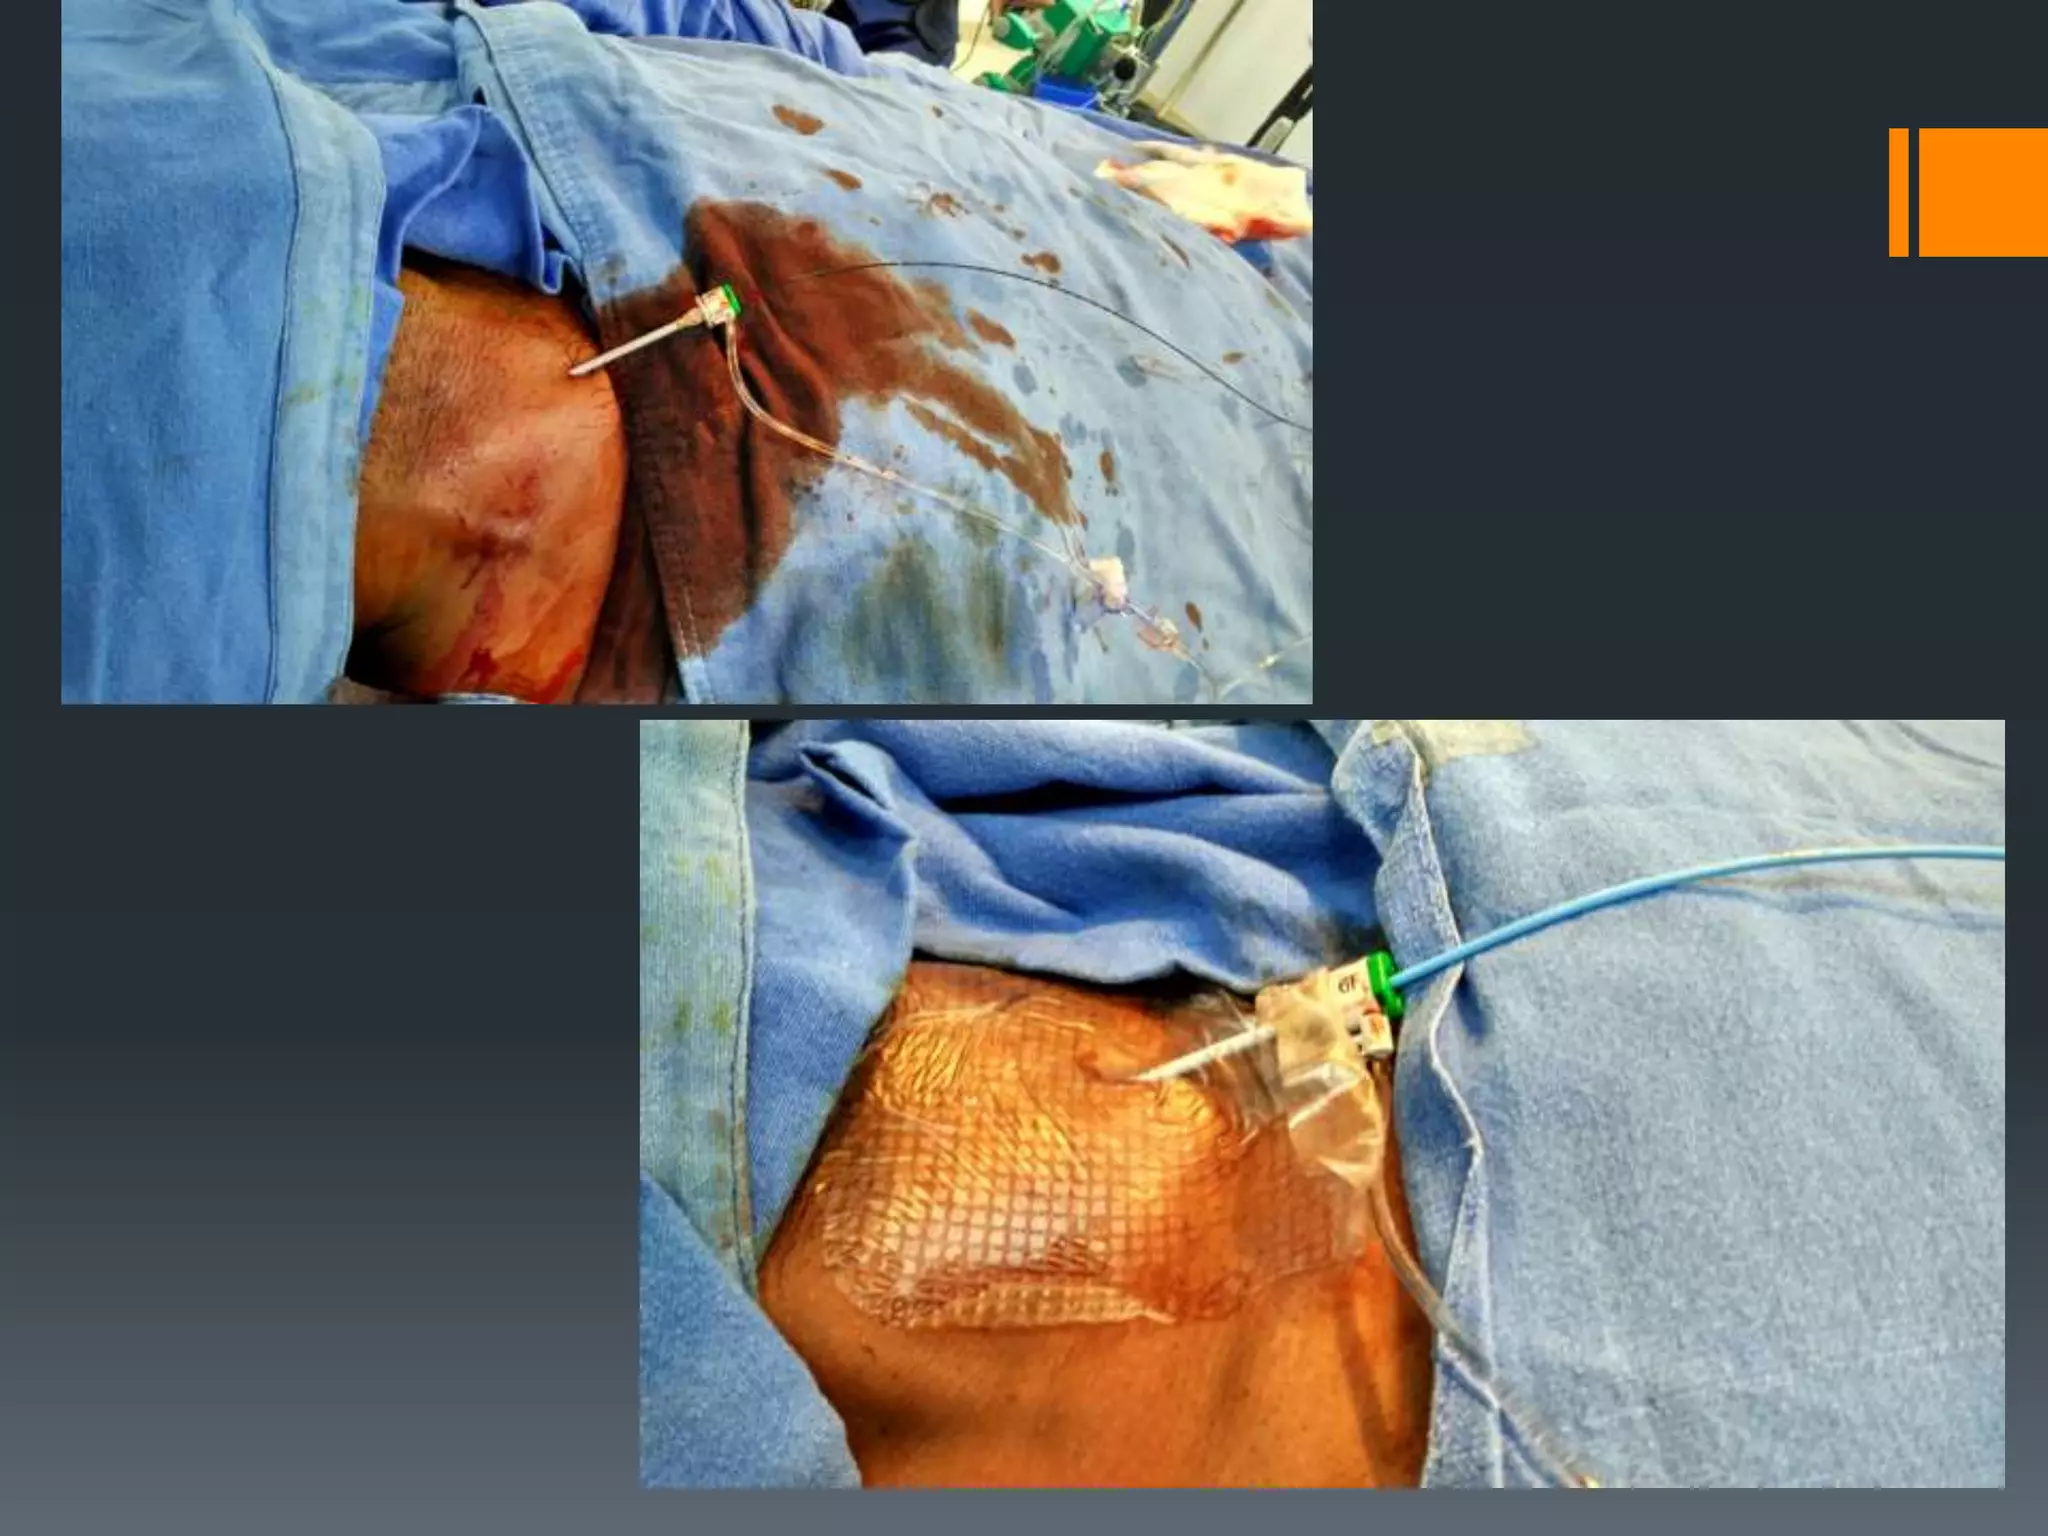

This document discusses tricks and techniques for difficult cannulations during neurointerventional procedures. It outlines strategies for accessing the aortic arch, internal carotid artery (ICA), and areas distal to aneurysms. Long sheaths, distal access catheters, and co-axial techniques are presented as options that have improved cannulation success. Guidance on sheath and catheter selection is provided for different vessel paths. The importance of catheter placement as high as possible in the ICA is emphasized. Reverse curve cannulations are also mentioned. Overall, the document stresses that careful cannulation is critical for procedural success and different strategies may be needed depending on the vessel target.